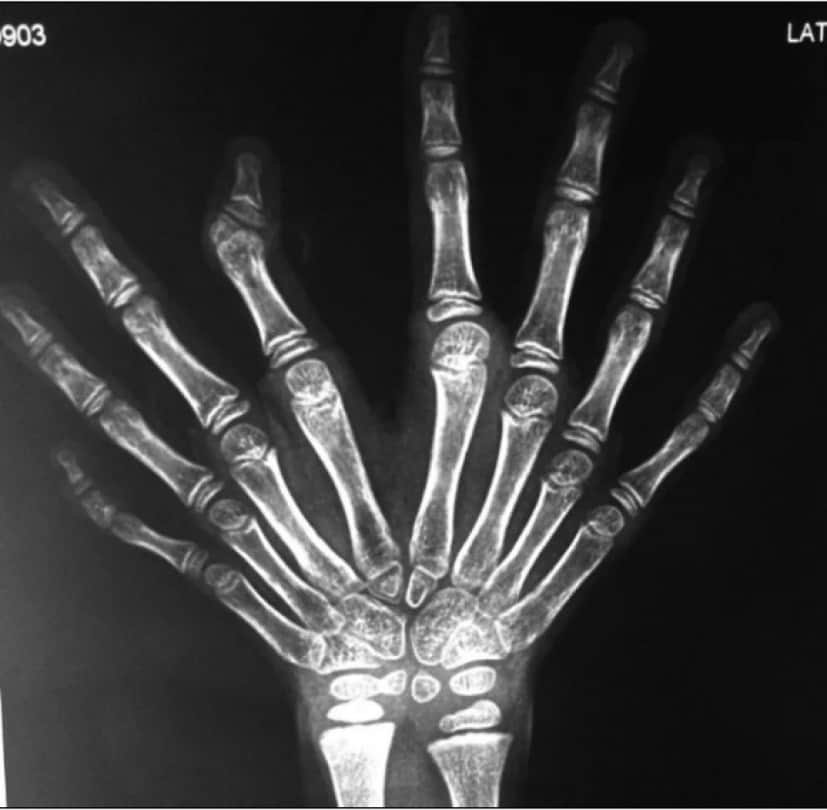

また、そのレントゲン画像も公開されていた

事実検証サイト、snopes.comによると、その真偽はいまだもって不明なのだそうだ。実際にミラーハンドと呼ばれる尺側重複肢症は存在する。

尺側重複肢症は稀な疾患で「尺骨が重複しているが、橈骨(とうこつ)と親指の不在」が見られる病である。ちなみに橈骨というのは尺骨と共に前腕に存在する2本の骨の長い骨の方(親指側)の事を言う。

1976年にスワンソン博士によってアメリカ手外科学会(ASSH)と手外科国際連盟(IFSSH)のガイドラインに基づき、第三群先天性異常に認定され、前例となるケースが幾つか存在している。

例えば2012年にインド、ビラースプルにおいてルペシュ・ナンデプ医師がミラーハンドを持つ7歳の少女を患者に受け持った経緯がある。この患者は片方の手に8つの指を持っていたという

以下の画像は重複尺骨病の患者のレントゲン写真である。尺骨のほかに、手根骨、中手骨、指骨の重複が認められ、橈骨と親指の不在が見受けられる。写真の人差し指の第二関節には形成不全も見受けられる。